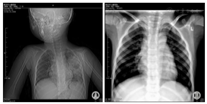

4例X线检查均示肺实质病变。例1,病程11 d CT示右上肺片状高密度影,病程20 d CT示双肺多个大小不等囊状影,右上肺显著。见图1A、图1B;3个月后复查胸片肺炎基本吸收,见图1C。例2,病程15 d肺CT:左侧胸廓略塌陷,左肺上叶大片状密实影,内见液平囊状影,见图2A、图2B;18个月后复查肺CT示左上肺脓肿消失,留有部分肺不张、条索影,见图2C。例3,病程6 d胸片示右上肺大片状高密度影,病程17 d肺CT示右上中肺大片及点状高密度影,右下肺背段多个厚壁空洞,呈簇状沿支气管分布,纵隔淋巴结大,见图3A、图3B。3个月后复查胸片肺炎基本吸收,见图3C。例4,病程5 d胸片示左上肺组织坏死,见图4A。0.5年后复查胸片提示炎症较前明显吸收,见图4B。

注:A:2010-04-30胸片示左上肺炎、肺脓肿;B:2010-11-22胸片示左上肺炎、肺脓肿基本吸收